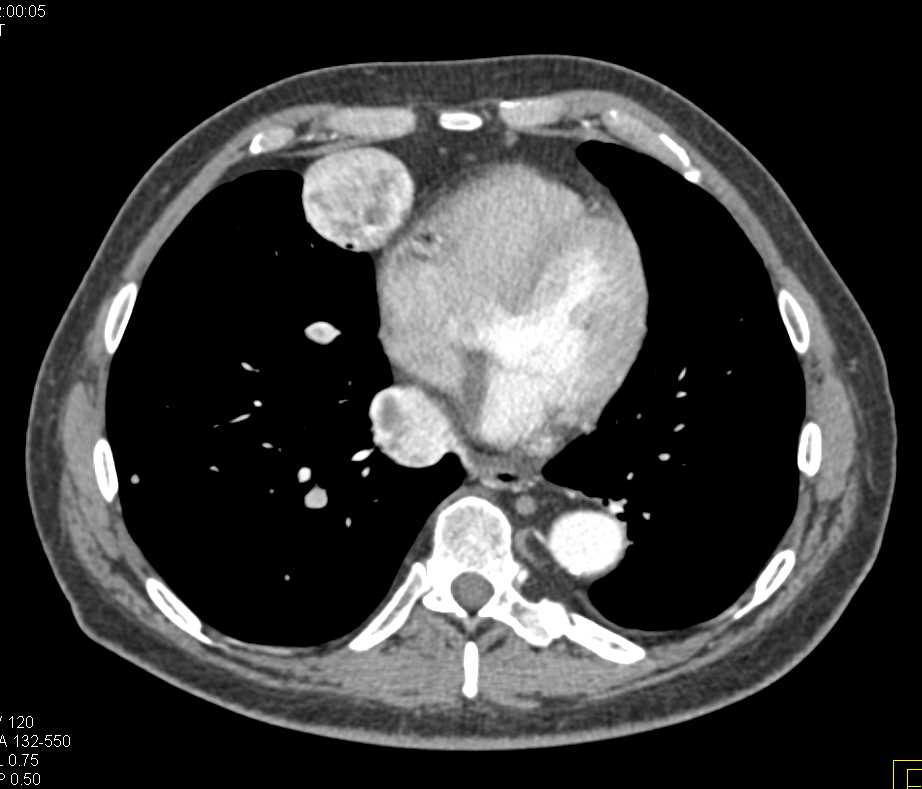

Bosniak 2F Cyst Left Kidney